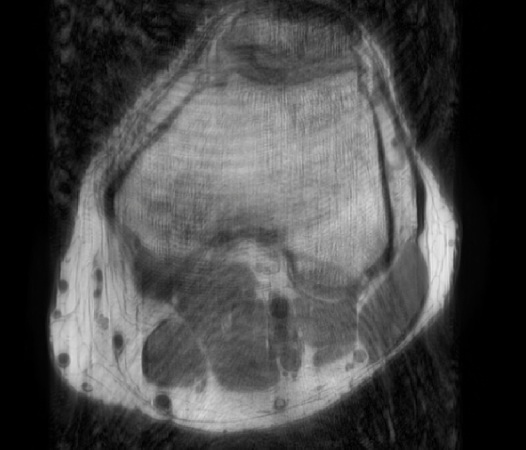

In the example below, only one fifth of the required MR radiofrequency signals is recorded. This results in a five times faster acquisition, with a subsampled k-space (top left) and inherent image artifacts after standard reconstruction (top right).

Knee with artifacts

Knee compressed sense

The Compressed SENSE reconstruction then uses iterative, knowledge-based algorithms to fill in the empty lines in k-space (bottom left). This removes the artifacts while keeping the final image fully consistent with the acquired data (bottom right).